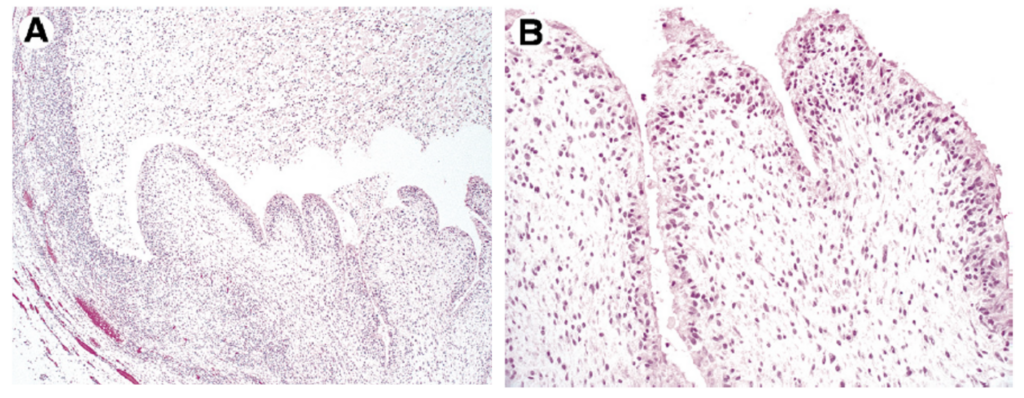

병소의 최종확인은 병리학적 검사 입니다.

입술점액낭종은 구강외과전문의에게는

정말 흔하게 접하는 케이스들중에 하나인데요

보통은 조직검사시 위 사진처럼 보이지만

간혹, 위사진처럼 다른 모양을 나타내는 경우도 있고

화생, 영어로는 metaplasia라로 하여

전혀 다른 조직학적 검사결과가

나오는 경우가 종종있기 때문에

반드시 조직검사가 필요합니다.

위 논문에서 1800여개의 병소중에

흔하지 않은 결과를 보인경우는 2개 뿐 이었지만

1800여번을 수술한 의사에게는 0.1%이지만

그 수술을 받은 환자에게는 100% 입니다.

조직검사 결과에 따라

치료가 종료되느냐, 상급병원진료를 이어가느냐가

결정되기 때문에

매교역치과 바른본에서는

양성종양제거 수술시에는

아무리 흔하고, 자주하는 수술이라고 할지라도

반드시

조직검사를 동반하고 있습니다.